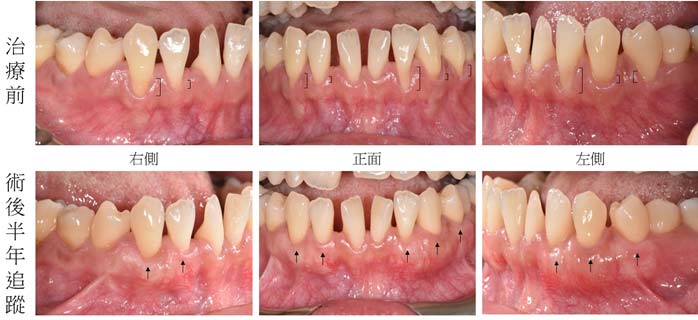

牙齦萎縮治療案例1 – 牙根覆蓋手術

先以牙根覆蓋手術治療,增加牙齦厚度後,後續再進行矯正治療。